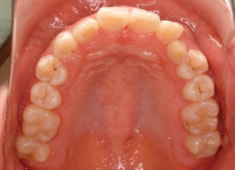

左上3番左下5番埋伏歯

治療前